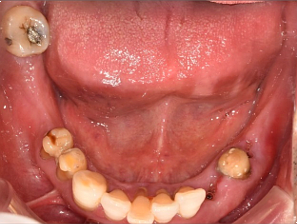

| 보험 임플란트 치료 사례 |

69세 남성

(전) 2021-11-05, (후) 2022-08-26

상기 환자분 오른쪽 아래 # 46, 47 어금니 2개 보험임플란트와 나머지 치아도 함께 치료받으신 사례입니다.

보험임플란트는 잇몸뼈가 충분하여 별도의 뼈이식술 없이 진행하였고요.

그 외 # 33 치아 임플란트를 식립하고, 그 옆에 # 34 치아는 크라운 씌워서 마무리했습니다.

그리고 # 35, 37에 임플란트 식립하고, 가운데 # 36 자리는 임플란트 폰틱(아래 사진 참고)이라 하여 브릿지와 같이 중간을 연결하는 가짜 치아로 시술해 드렸습니다.

전후 사진을 보시면 상당 부분 비어있던 치아들이 메워져 음식 섭취는 물론이고 심미적인 측면으로도 훨씬 개선된 모습을 확인하실 수 있습니다. ^^